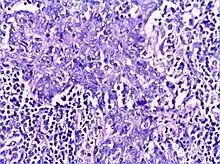

There is a marked lymphoplasmacytic infiltration. Lymphoid follicles surround solid epithelial nests, giving rise to the 'epimyoepithelial islands', that are mainly composed of ductal cells with occasional myoepithelial cells. Excess hyaline basement membrane material is deposited between cells, and there is also acinar atrophy and destruction.